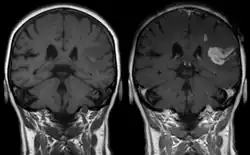

- Magnetresonanztomographie

Die Magnetresonanztomographie (MRT) ist als bildgebendes Verfahren zu unempfindlich, um die Passage von Wirkstoffen in das Gehirn darzustellen. Völlig anders ist die Situation bei einer geschädigten Blut-Hirn-Schranke. In diesen Fällen spielt die kontrastmittelunterstützte MRT als diagnostisches Verfahren bei verschiedenen neurodegenerativen Erkrankungen und Krebserkrankungen im Bereich des Gehirns eine wichtige Rolle. Dies wird im Kapitel der mittelbar mit der Blut-Hirn-Schranke assoziierten Erkrankungen ausführlicher beschrieben.

Bereits kurz nach der Entwicklung von Gadopentetat-Dimeglumin (Gd-DTPA), dem ersten Kontrastmittel für die Kernspintomographie, 1984,[236] wurde das Potenzial der kontrastmittelverstärkten Magnetresonanztomographie für die Diagnose von lokalen Störungen der Blut-Hirn-Schranke erkannt.[237] Gd-DTPA ist als hochpolares Molekül viel zu hydrophil, um die gesunde Blut-Hirn-Schranke passieren zu können. Veränderungen an den Tight Junctions, wie sie beispielsweise durch Glioblastome ausgelöst werden, ermöglichen den parazellulären Transport dieses Kontrastmittels in das Interstitium. Dort verstärkt es durch die Wechselwirkung mit den Protonen des umgebenden Wassers den Kontrast und macht so die defekten Bereiche der Blut-Hirn-Schranke sichtbar. Da diese Blutgefäße für die Versorgung des Tumors zuständig sind und sich zu diesem in unmittelbarer Nachbarschaft befinden, lässt sich so das Ausmaß des Tumors darstellen.

Bei einem akuten ischämischen Schlaganfall kann die Störung der Blut-Hirn-Schranke ebenfalls durch kontrastmittelverstärkte MRT zur Diagnosestellung herangezogen werden.[238]

Durch die Bestimmung der Relaxationszeit kann die Menge an Gd-DTPA im Interstitium quantifiziert werden.[239]